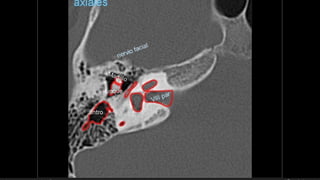

Evaluación Imagenologica

• #38 Izqu. AXIAL-- fxLongitudinal perdonan la capsula otica (laberinto oseo) Centro AXIAL fx trnasversa lascuales tperdonan el lab erinto oseo Dere: MIXTA – tmp perdona

• #48 cochlear aqueduct, vestibular aqueduct Gs Sulcum glosofaríngeo Jf foramen yugular

• #52 AXIAL Frctua canal carotideo